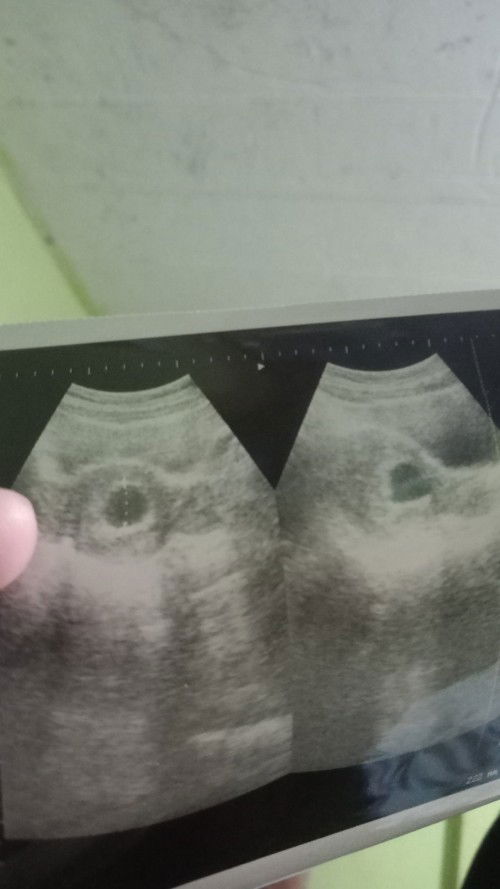

Janin tidak berkembang

Janin tidak berkembang usia 12 minggu. Hanya ada kantong saja. Disarankan kuret, kehamilan pertama dan paling ditunggu. Sedih liat pasien lain pada ada baby disampingnya. Aku malah kuret😢